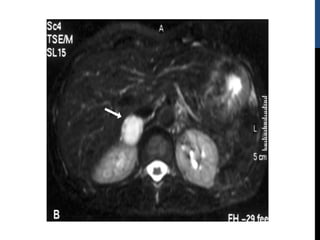

TAC Y RMN

Por su tamaño (típicamente entre 2 y 5 cm) los

feocromocitomas son tumores fácilmente detectables tanto

por TC como por RM

La sensibilidad de la TC es superior al 93%

En la RM el feocromocitoma muestra característicamente

isointensidad respecto al hígado en T1 y es en cambio

hiperintenso respecto al hígado y a tumores suprarrenales

de otra estirpe en T2

La hipervascularización del tumor es evidente si se usa

gadolinio.

•   EN BUSQUEDA DE METASTASIS: INCIDENTALOMA SUPRARRENAL

IZQUIERDO EN TAC ABDOMINAL.

•   COMPLEMENTÓ PROTOCOLO DIAGNÓSTICO: Metanefrinas en orina de

4943 (35 – 460 mcg en 24 hrs) Normetanefrinas en Orina 2598 (110 – 1050

mcg en 24 hrs) Calcitonina 372 pg/ml (<11.5 pg/ml). Se solicitó RMN que

demostró LESIONES OCUPANTES DE ESPACIOS SUPRARRENALES

BILATERALES.